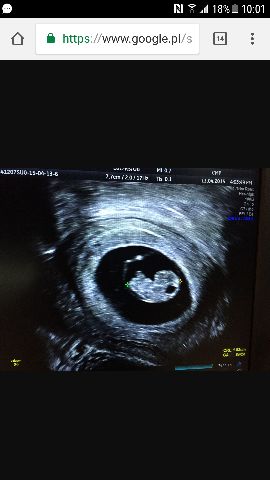

Ja dzisiaj 7+4 następna wizyta 5 grudnia i wtedy będzie 9+1Dzidzia ma 9tyg, rozpoczęliśmy wczoraj 11 tydzień ciąży [emoji7] a Ty przypomnij mi?

Nie wiem od kiedy dzidzia przypomina dzidzie bo to moje pierwsze usg, bo na ost był tylko pęcherzyk.

Tu znalazłam na mamaginekolog dziecko ma 1.80cm i już wygląda powoli jak mały człowiekJa dzisiaj 7+4 następna wizyta 5 grudnia i wtedy będzie 9+1![]()

DziękujęTu znalazłam na mamaginekolog dziecko ma 1.80cm i już wygląda powoli jak mały człowiek

Wg tej strony dzidzius 7 tyg ma 7-12mm

Nie wiem na ile się to "zgadza" - u mnie pasuje, dziecko ma 9tyg, i 2.5 cm więc wg tej strony pasuje